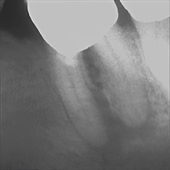

Die Entzündung im Knochen ist so stark ausgeprägt, dass sie bereits über eine "Zahnfistel", aus der sich Eiter entleert, nach außen durchgebrochen ist. Diese Fistel ist hier mit einem Kontrastmittel dargestellt. Früher sicher ein Anlass, diesen Zahn sofort zu ziehen oder zumindest einen chirurgischen Eingriff (Wurzelspitzenresektion) mit Verkürzung der Wurzeln vorzunehmen.